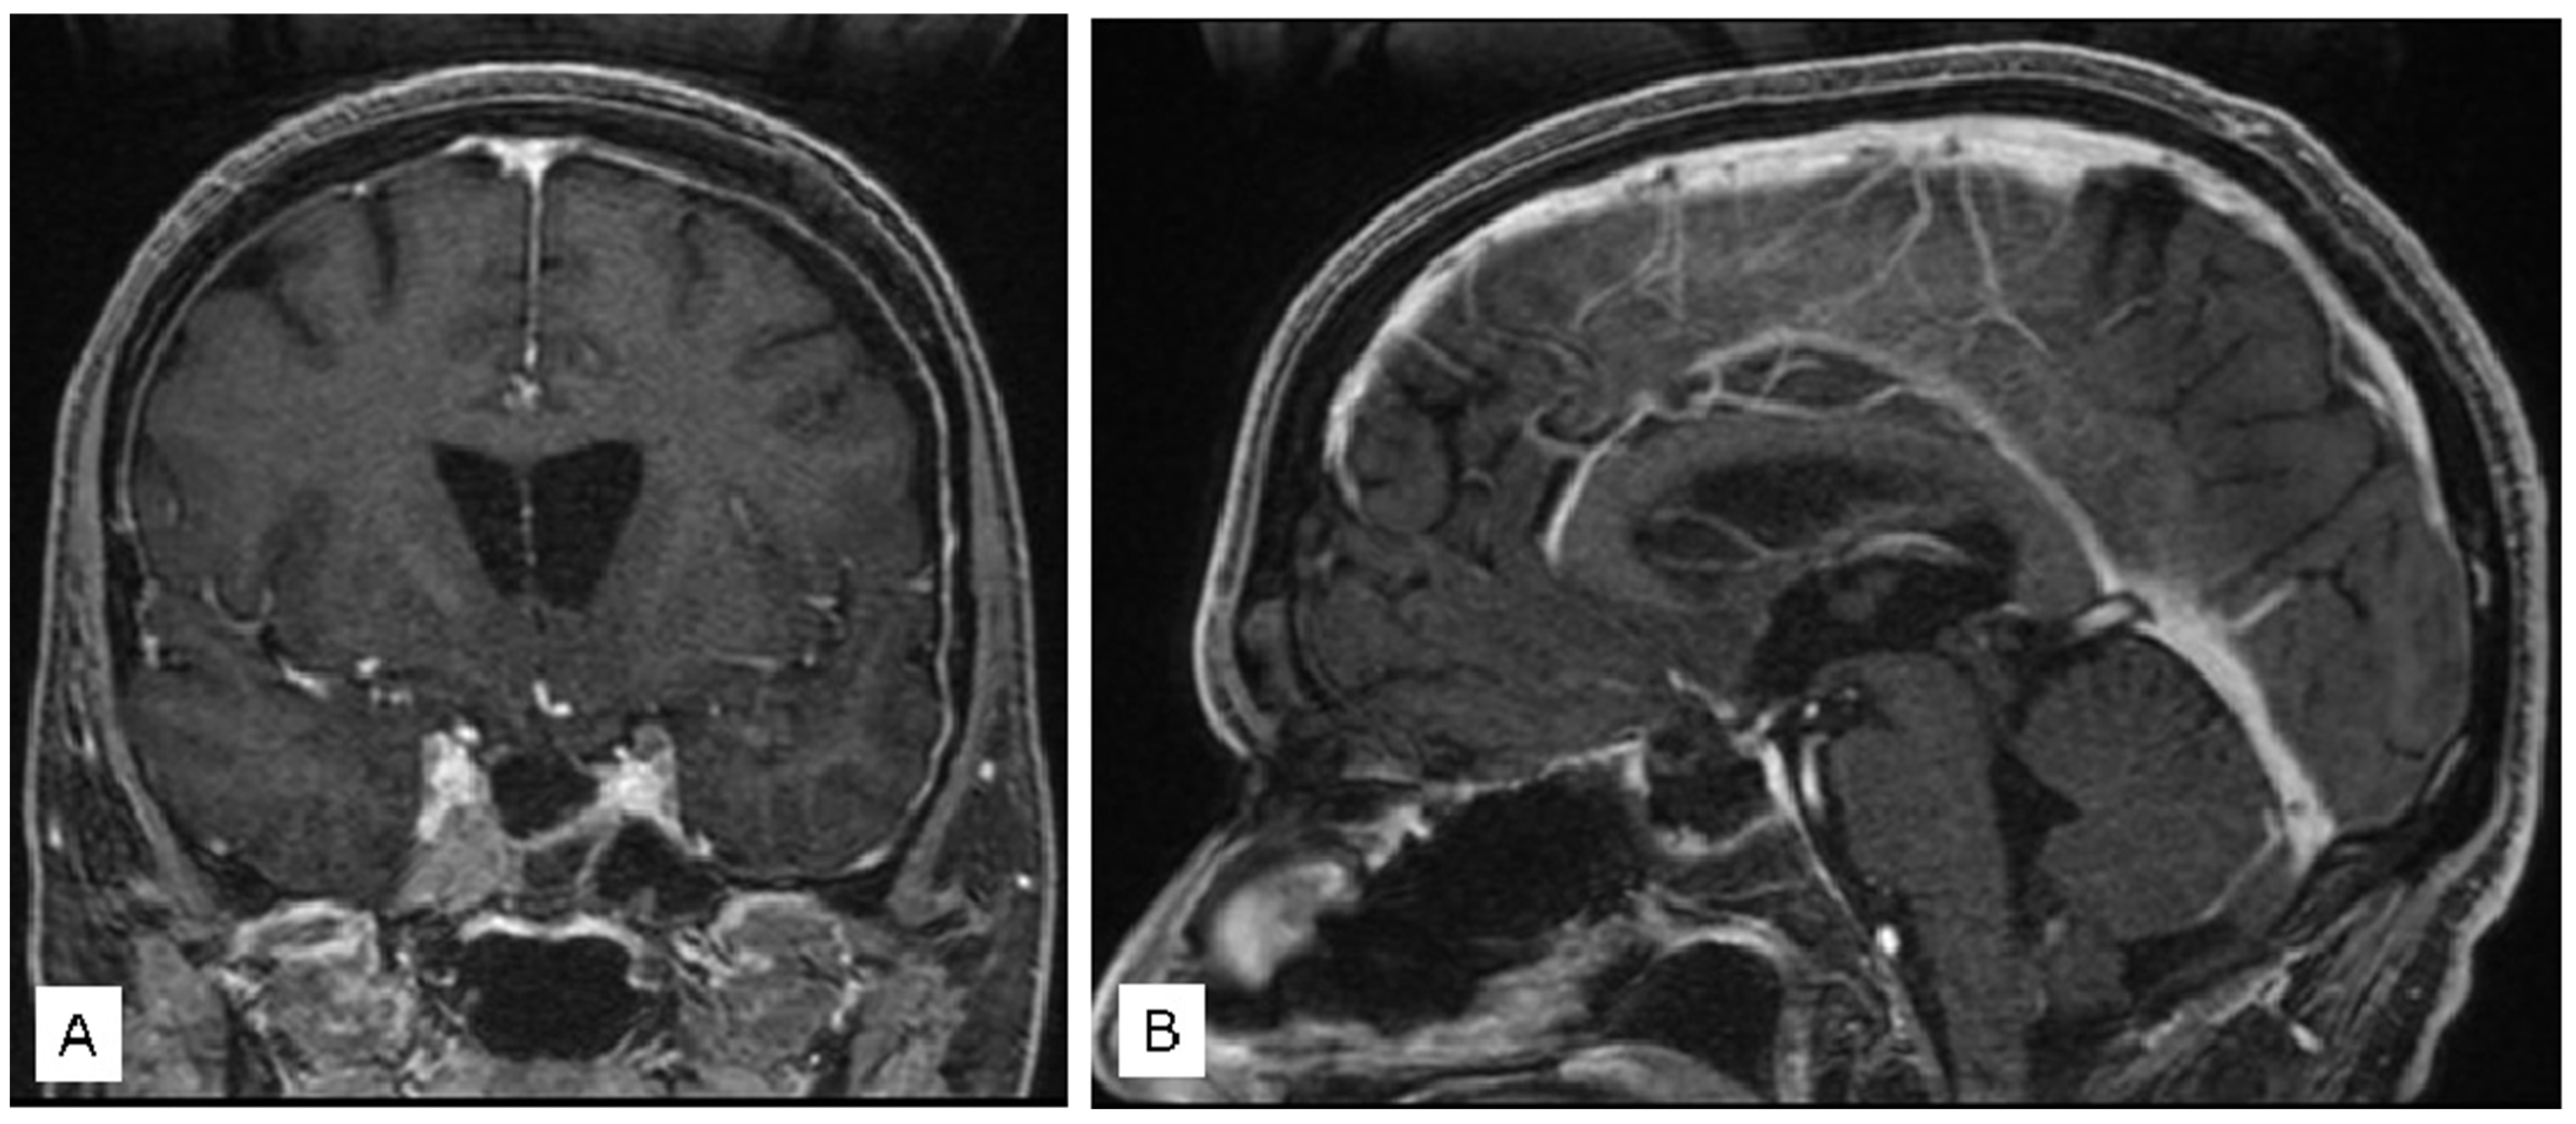

3.1.2. Case 2